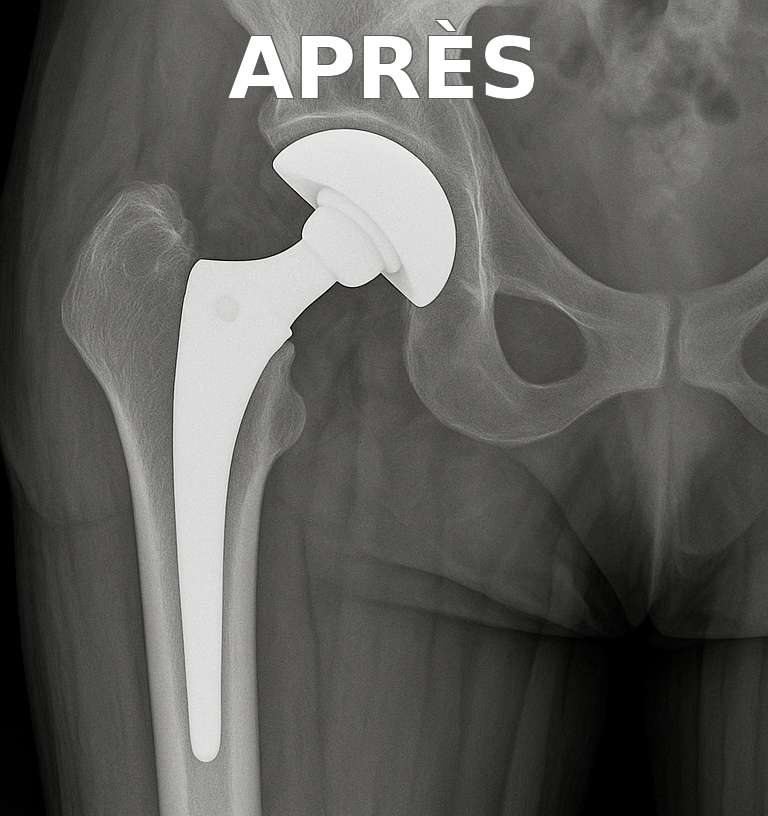

Illustration radiologique

Prothèse de hanche